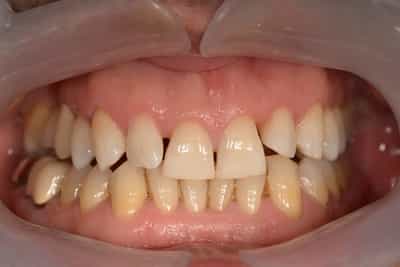

L’éclaircissement dentaire est une technique consistant à rendre aux dents une couleur plus harmonieuse, plus en adéquation avec l’image que le patient veut donner de lui. Le blanc des yeux est une référence. A l’échelle du visage, la blancheur de la sclérotique de l’oeil (blanc des yeux) fait ressortir la couleur jaune des dents. Pour une meilleure harmonie, il faut aligner ces deux couleurs. Si les dents sont moins lumineuses, l’éclaircissement va améliorer l’apparence. Après éclaircissement, cette différence s’atténuera et donnera une harmonie du visage.

Souvent, à partir d’un certain âge, les dents changent de couleurs. Ces changements peuvent être dûs à des colorations extrinsèques. Dans ces cas, un simple nettoyage-polissage peut suffire à y remédier.

Dans d’autres cas, il s’agit d’une usure de l’émail. L’émail est responsable de la luminosité de la dent, et son usure a tendance à révéler la couleur de la dentine sous-jacente. Elle peut être marron, jaune, grise, orange… L’éclaircissement agit sur les colorations intrinsèques et extrinsèques, en surface et en profondeur.

On distingue deux types d’éclaircissement:

-le blanchiment externe : il concerne les dents vivantes et consiste à l’application d’un gel éclaircissant sur l’extérieur des surfaces dentaires. Cette technique de homebleaching nécessite obligatoirement l’accompagnement de votre dentiste. Il faut savoir gérer les éventuelles sensibilités pouvant apparaitre dans de rares cas. Le blanchiment doit être encadré dans son protocole et sur toute sa durée.